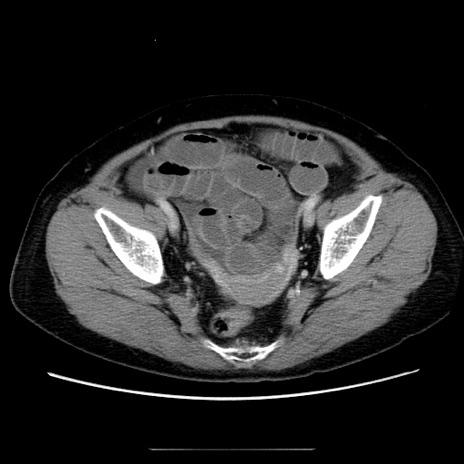

冠状断像

【症例】70歳代女性

【主訴】お腹が張る

【現病歴】1週間くらい前から腹部膨満の自覚あり。昨日夜から増悪したため、本日救急外来受診。

【身体所見】意識清明、BT 36.5℃、BP 165/106mmHg、HR 80bpm、SpO2 98%、腹部:膨満、軟、自発痛・圧痛なし、触診にて不快感あり、腸蠕動音:減弱

【データ】WBC 12600、CRP 1.04